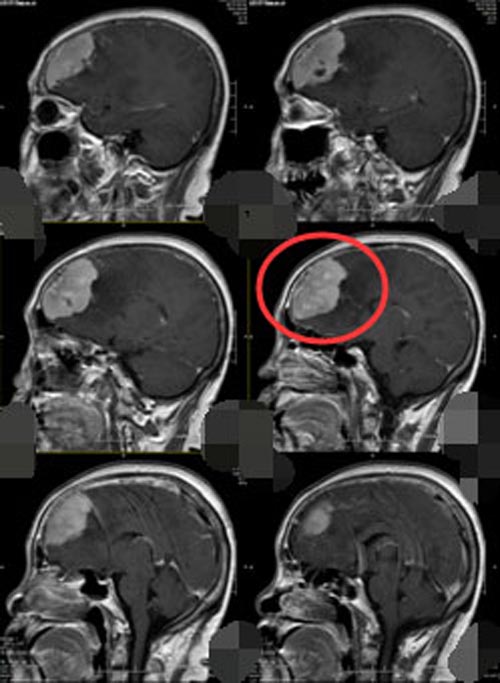

排除手术禁忌症后,神经外五科手术团队在全麻下行“左侧额部大脑镰窦旁脑膜瘤切除+左侧大脑中动脉动脉瘤夹闭术”,术中导航定位,切开额部硬脑膜后,局部脑组织肿胀严重,可见暗红色肿瘤, 分块切除后,可见坏死组织血供丰富,与大脑镰和矢状窦密切相连,仔细分离全切后,又取左侧翼点入路,充分暴露大脑中动脉M1M2段上下干后,可见上干有一3mm×2mm的囊状动脉瘤,小心夹闭后予术中TCD检测,吲哚菁绿造影展示大脑中动脉M1和M2段上下干保留完好,麻醉满意,手术顺利。术后病理检验结果示:左额脑膜皮细胞型脑膜瘤,WHO I 级,本例细胞增生活跃。术后头颅CT示:左额脑膜瘤切除术后+左侧大脑中动脉瘤夹闭术后。

▲手术前